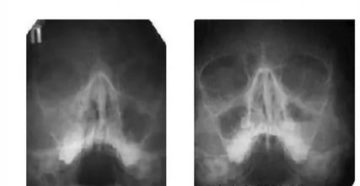

Что такое субтотальное затемнение гайморовых пазух Субтотальное затемнение гайморовых пазух – что это и насколько…